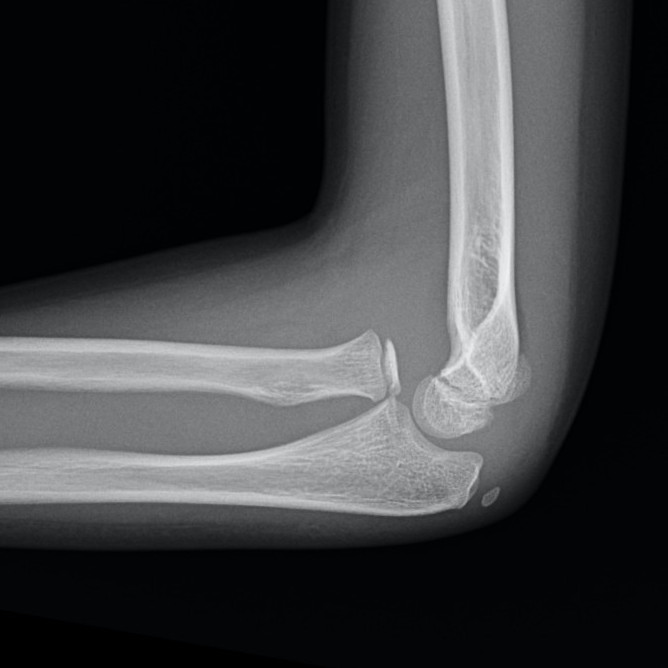

Case 2. Chronic Monteggia with deformed radial head